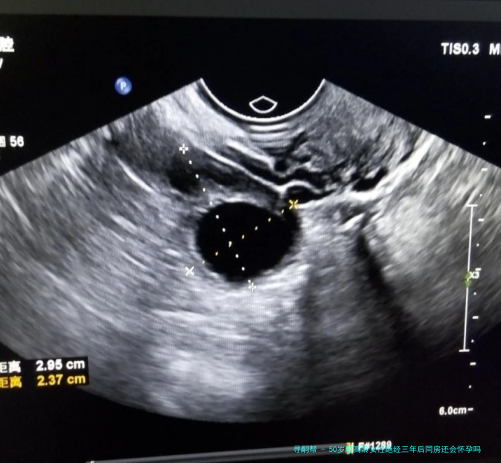

50岁超高龄女性绝经三年后同房还会怀孕吗?

上一次看1个新闻说是大龄女性绝经后仍然怀孕,我就记忆挺不堪设想的,我原本来是不信的,但是我怕无数朋友都说是有这种案例存在的,但是我在想不是闭经随后,卵巢功效会下降吗,不是应该相比难以怀孕了呀,并且也不来大例假了,为什么还会出现这类情况呀,有姐妹知道上了50岁的超高龄女性,在绝经三个年头后又会怀孕吗?